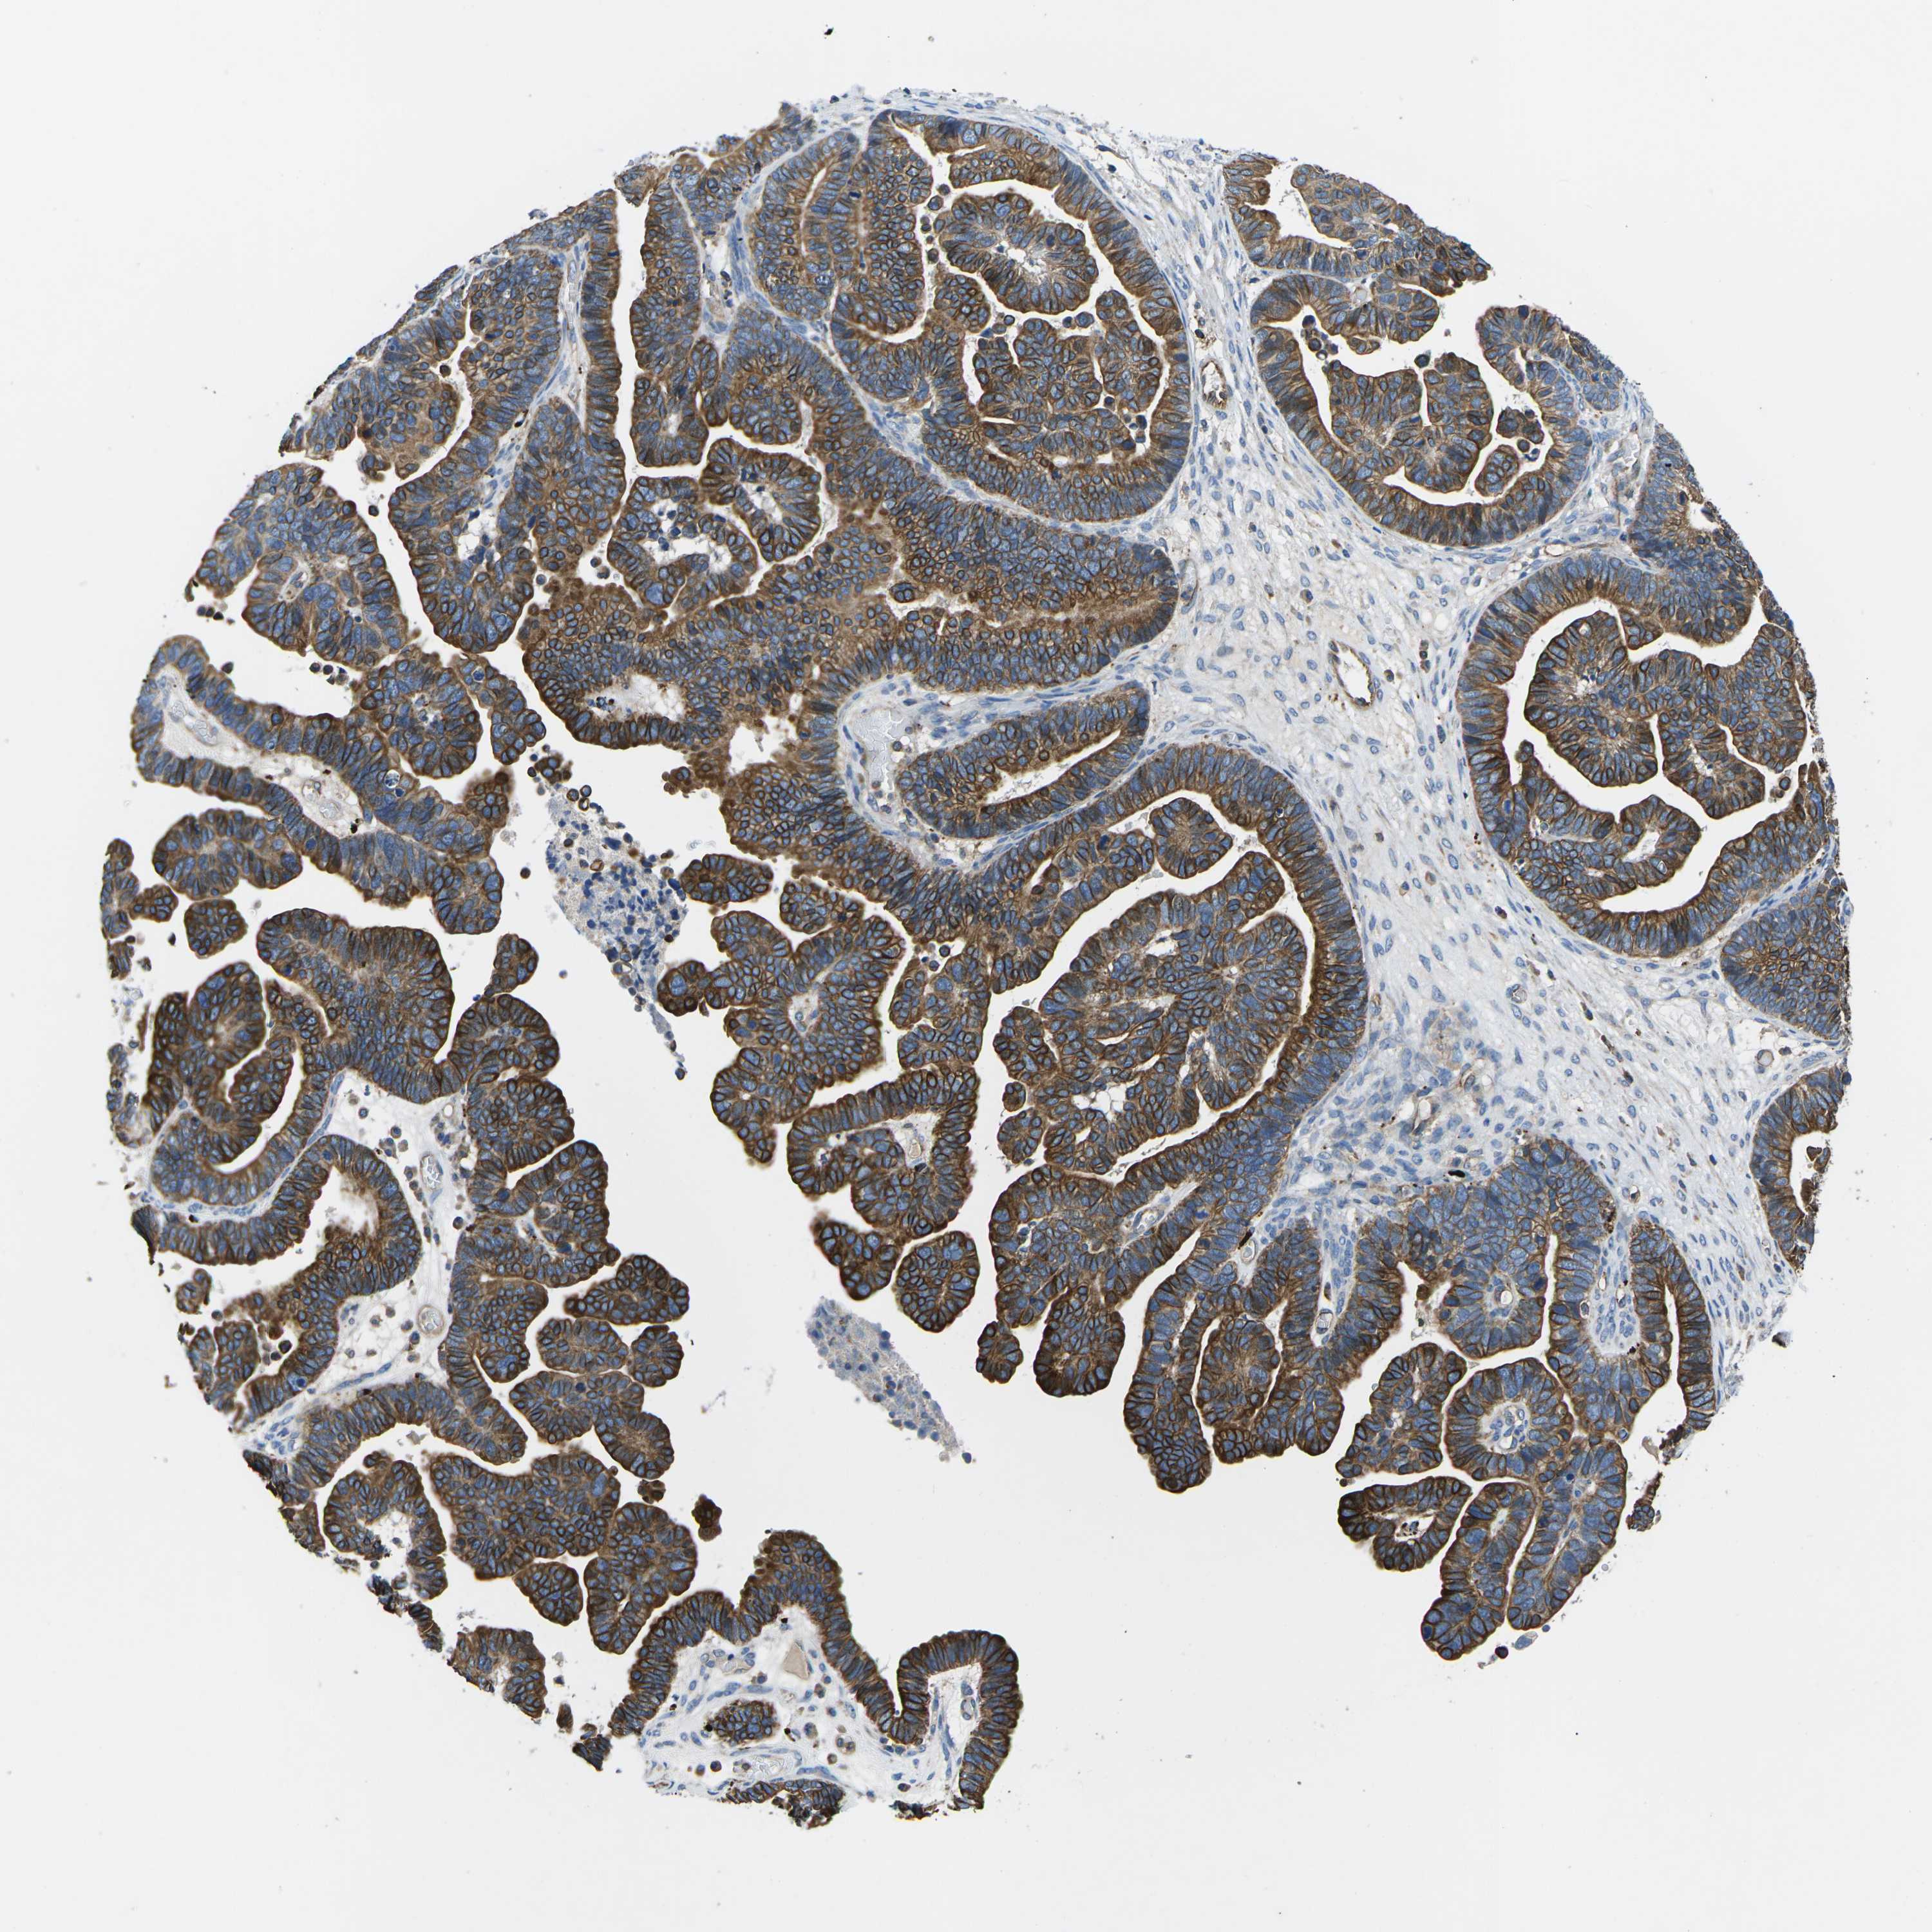

OVARIAN CANCER - Protein expressioni

A mouse-over function shows sample information and annotation data. Click on an image to view it in a full screen mode. Samples can be filtered based on level of antibody staining by selecting one or several of the following categories: high, medium, low and not detected. The assay and annotation is described here.

Note that samples used for immunohistochemistry by the Human Protein Atlas do not correspond to samples in the TCGA dataset.

Antibody stainingi

Antibody staining in the annotated cell types in the current human tissue is reported as not detected, low, medium, or high, based on conventional immunohistochemistry profiling in selected tissues. This score is based on the combination of the staining intensity and fraction of stained cells.

Each image is clickable and will lead to virtual microscopy that enables deeper exploration of all samples and also displays staining intensity scores, fraction scores and subcellular localization as well as patient and tissue information for each sample.

Antibody HPA016702

Staining

High

Medium

Low

Not detected

Intensity

Strong

Moderate

Weak

Negative

Quantity

>75%

75%-25%

<25%

None

Location

Nuclear

Cytoplasmic/membranous

Cytoplasmic/membranous,nuclear

Cystadenocarcinoma, serous, NOS

Carcinoma, endometroid

Cystadenocarcinoma, mucinous, NOS

Carcinoma, NOS